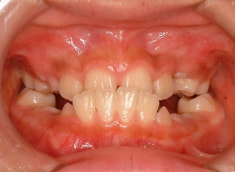

治療前

治療後(12ヶ月後)